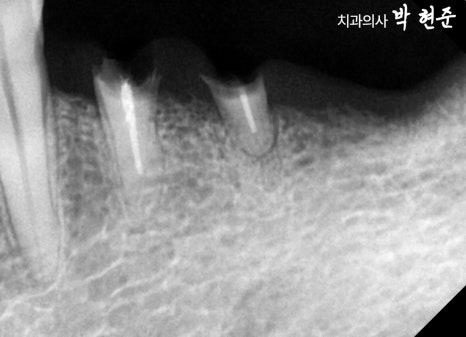

엑스레이 예시 사진을 관찰해보니

치관의 많은 양이 부러진 것으로 보여집니다.

이미 과거에 근관치료도 받았던 곳으로 보이기에

발치가 필요하겠습니다.